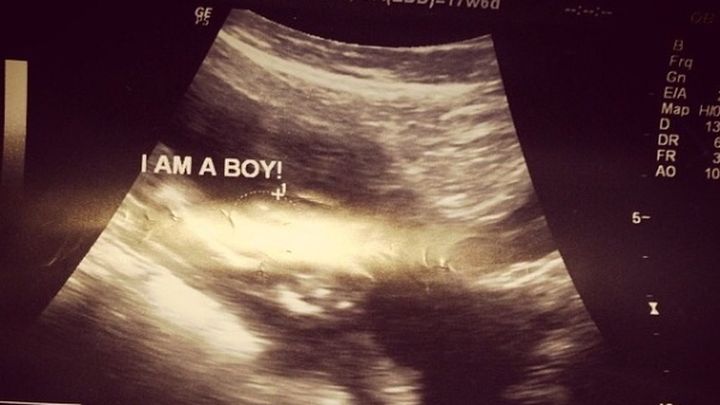

My husband and I have been married for five years. We had been trying to get pregnant with little success, until one day surprisingly I found out I was expecting. Not knowing my underlining issues, I did what any newly expecting mother did; attended my doctor visits, took my vitamins and shared the overwhelming joy with my family. On May 22, 2014, after unexpectedly having been in labor for about 8 hours, and only at 19 weeks I gave birth to my first son Austin Nasir Theus. He weighed only 225 grams. I was completely devastated. My world was turned upside down. I asked the doctors to do everything, but in the state of Texas a baby is not viable until 24 weeks.

The next month was emotional. Having to bury a child was hard. I tried remaining positive knowing everything happens for a reason. Approximately around the end of July into August, I then found out I was expecting again; quickly I know, but I was excited. I started my prenatals and taking extra care of myself so I wouldn't have to revisit another tragedy, or so I thought. My doctor labeled me "high-risk", because of the first mishap. Overtime, things seem to be well. I had finally did well enough to pass the 19th and then 20th week. We were certain that my first loss was surely spontaneous. On December 20, 2014 at 21 weeks I gave birth to my second baby boy Aden Muhammed Theus.  Adens birth was even harder to bare I never thought this would be happening again.